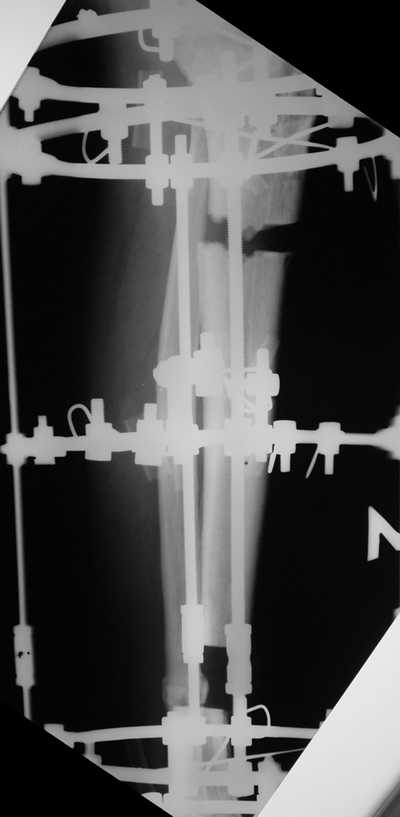

Мужчина, 33 года, резекция б\б кости по поводу остеомиелита после открытого

перелома. Стандартная методика билокального остеосинтеза (рис 1 и 2). В

конце удлинения выявилось неудовлетворительное взиморасположение

перемещенного фрагмента и дистального отломка (рис 3). Планирование (рис 4).

Адаптация отломков гексаподом за 5 дней (рис 5). Замена гексапода на обычные

штанги (рис 6 и 7)